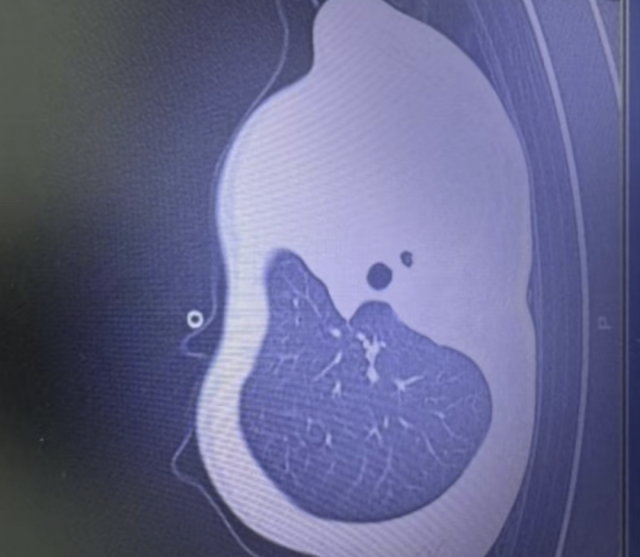

国内周二也爆出一名1岁男童病例,就因为感染流感病毒,短短一天的时间,就从轻微发烧咳嗽直接发展到肺堵死,出现“白肺”缺去鬼门关走了一遭!